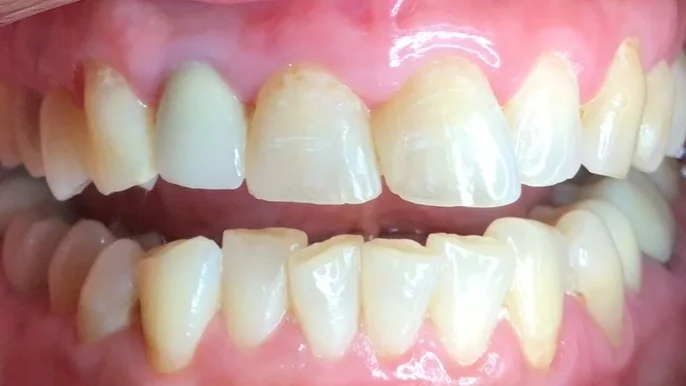

Cosmetic Resin Bonding